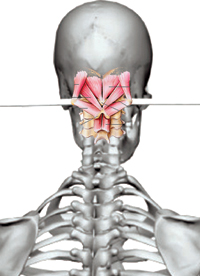

Súlyos testi és lelki panaszainak megoldását keresve René Claudius SCHÜMPERLI az 1993-1996-ig tartó intenzív kutatásai során rádöbbent arra, hogy a koponya-atlasz ízületben az Atlasz (első nyakcsigolya) szinte minden embernél ficamszerűen elfordult állapotban van. Megállapította azt is, hogy az atlasz elfordulását változó mértékű elbillenés is kíséri. Tehát a koponya alátámasztottsága nem vízszintes, és változó mértékű és súlyosságú egyensúlytalanság lép fel. A […]]]>

Súlyos testi és lelki panaszainak megoldását keresve René Claudius SCHÜMPERLI az 1993-1996-ig tartó intenzív kutatásai során rádöbbent arra, hogy a koponya-atlasz ízületben az Atlasz (első nyakcsigolya) szinte minden embernél ficamszerűen elfordult állapotban van. Megállapította azt is, hogy az atlasz elfordulását változó mértékű elbillenés is kíséri. Tehát a koponya alátámasztottsága nem vízszintes, és változó mértékű és súlyosságú egyensúlytalanság lép fel. A […]]]>

Igen, elmondható, hogy az atlasz rossz pozíciója idővel számos belszervi, idegi, csontrendszeri és pszichés panaszokat hoz ránk, ami rontja a munkaképességet, fájdalmakat okoz és kihat az életkilátásunkra is, – falja az életenergiánkat. Ha kificamodik valamelyik testrészünk – vállunk, bokánk, ujjpercünk – az nagy fájdalommal és jól látható alaki eltéréssel jár, amitől mielőbb meg akarunk szabadulni. Mentőt hívunk, […]]]>

Igen, elmondható, hogy az atlasz rossz pozíciója idővel számos belszervi, idegi, csontrendszeri és pszichés panaszokat hoz ránk, ami rontja a munkaképességet, fájdalmakat okoz és kihat az életkilátásunkra is, – falja az életenergiánkat. Ha kificamodik valamelyik testrészünk – vállunk, bokánk, ujjpercünk – az nagy fájdalommal és jól látható alaki eltéréssel jár, amitől mielőbb meg akarunk szabadulni. Mentőt hívunk, […]]]>